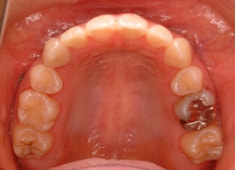

上顎前突+右下7番重度埋伏

(右下7番目の永久歯が下顎の中に埋まったまま、親知らずが上に乗っている)

治療法:フルパッシブブラケット:T21

解説:右下7番を抜歯し、右下8番を開窓牽引しました。近年、顎が退化しており、歯の大きさとの不調和がどんどん強くなりつつあります。2018年の矯正学会でも、本症例と同様の下顎7番8番の問題ケースが講演で紹介されておりました。こうなる前に、先手を打ちたいものです。小児の間に先行治療できるのがベストですので、お子様が6才になったら矯正専門医院に初診相談に行くようにしましょう。やる必要があるかどうかを聞きに行くのです。

治療前